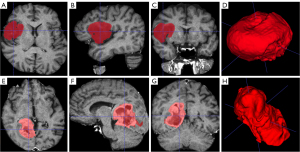

Several pre-processing steps were made using scripts from FSL library. Susceptibility distortion correction was done by the “topup” algorithm followed by eddy current and movement artifacts correction by the “eddy” algorithm (18,19). Scull striping was done by “bet” algorithm and anatomical T2-weighted image was registered into b=0 space by linear rigid (6 degrees of freedom) registration using the “FLIRT” algorithm. The binary masks of segmented tumours were registered into the DWI space by the same registration matrix as used for the T2-weighted image in the previous step. The first multi-b diffusion analysis was based on the IVIM model. For fitting of IVIM parameters [f, D*, and D (diffusion)], algorithms from the Diffusion in Python (DIPY) (20) library were used together with the optimization process method known as “variable projection”, which utilizes an MIX approach with bounds 0–0.8 for f, 0–0.1 mm2/s for D*, and 0–0.01 mm2/s for D and all available b-values were used (21). Additional multi-b diffusion analysis was based on a diffusion kurtosis model wherein parameters of diffusion and kurtosis (K) were fitted by logarithmic fitting option in Medical Imaging Interaction Toolkit (MITK) software with boundaries from 0 to 3 and smoothing sigma equal to 5 and all available b-values were used (22,23). For the subsequent statistics, only the diffusion parameter (D) calculated by IVIM model was used and not the one calculated by the diffusion kurtosis model. Examples of multi-b parameter maps and 3D volumes of interests (VOIs) in patients with gliomas are presented in Figures 2-4.ASL normalization by proton density-weighted images as well as CBF maps were calculated automatically by hardware-related Philips software. ASL image was subsequently registered to DWI b=0 space by linear rigid (6 degrees of freedom) registration using the “FLIRT” algorithm. For the final analyses, the same binary segmentation masks as in multi-b analyses were used.

Figures 2-4 show examples of parametric maps and 3D VOIs in patients with HGG (Figure 3) and LGG (Figure 4).